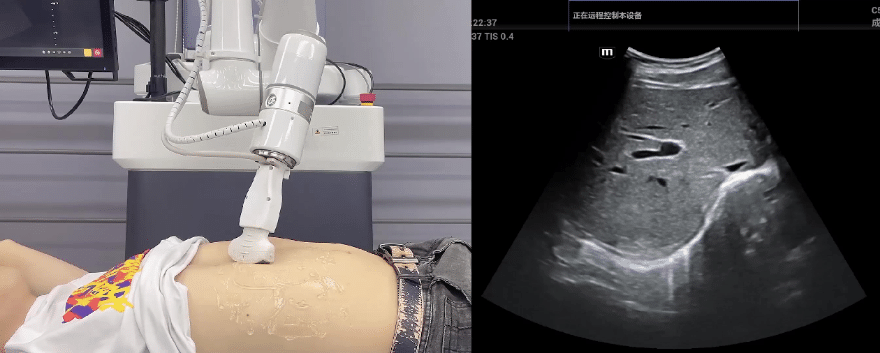

NG28娱乐协作机器人搭载库柏特自主研发的机器人遥操作、多模态数据采集与处理、机器人模仿学习、机器人力位控制等技术升级变革传统超声,可实现远程+自主超声扫查与诊断,从传统远程超声仅能对话会诊变革升级为能对话、能操作,使得基层患者可就近享受异地三甲专家扫诊服务。实现专家端与患者端远程连接,并支持专家端与多路患者端自由切换控制。

EC66协作机器人末端可搭载主流品牌高品质超声仪,让操作指令和影像低延迟、高精准、高保真传输,确保检查可靠、医患放心;智能力控等三重防护系统,确保患者舒适、安全。

NG28娱乐协作机器人与超声深度打通,最大程度保留医生左右手同时操作传统超声的习惯,并改善其舒适性,超声检查实际应用场景展示如下:

肝脏、胆囊、胰腺扫查